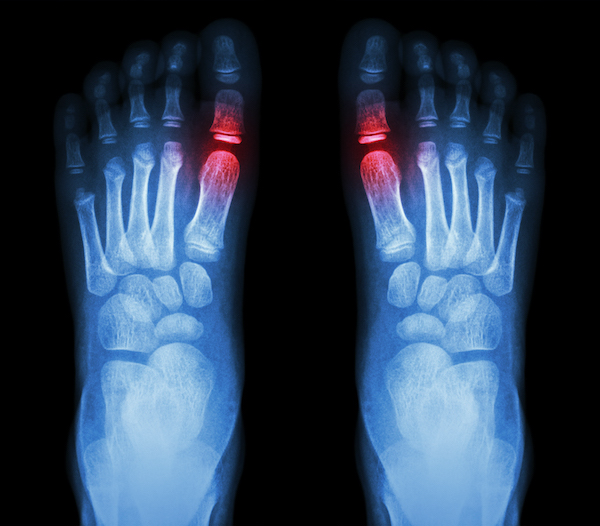

From www.sciencephoto.com

Osteoarthritis of Big Toe, Xrays Stock Image C027/2784 Science Arthritis In Big Toe Only It typically occurs as a result of wear and tear or overuse. It causes pain and stiffness in your mtp joint. It is one of the most common arthritic conditions affecting people ages 30 to 60. It can cause stiffness, pain, numbness, and changes in gait. Hallus rigidus or stiff big toe is when arthritis affects the big toe. What. Arthritis In Big Toe Only.

Osteoarthritis of Big Toe, Xray Stock Image C027/2782 Science Arthritis In Big Toe Only (also known as big toe joint osteoarthritis) a common condition that affects the big toe joint known as 1st metatarsal phalangeal joint. Osteoarthritis of the big toe is a condition that causes pain and stiffness in the joints of the big toe. It is one of the most common arthritic conditions affecting people ages 30 to 60. Hallux rigidus is. Arthritis In Big Toe Only.

Osteoarthritis Of Big Toe Stock Image C030/5911 Science Photo Library Arthritis In Big Toe Only It is the most common arthritic condition of the foot, affecting 1 in 40 people over the age of 50 and typically developing in. It causes pain and stiffness in your mtp joint. Osteoarthritis of the big toe is a condition that causes pain and stiffness in the joints of the big toe. (also known as big toe joint osteoarthritis). Arthritis In Big Toe Only.